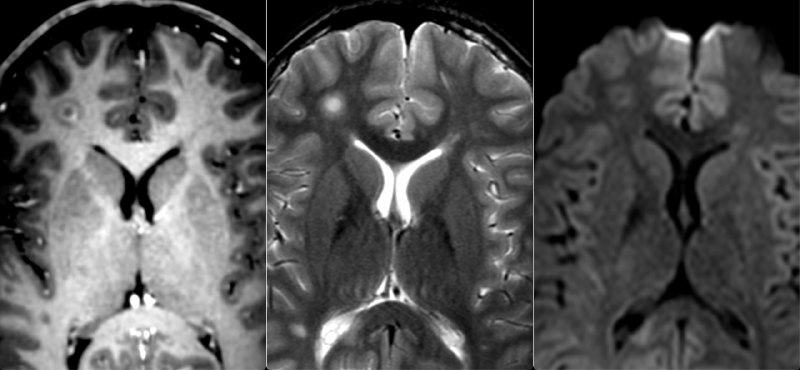

картинку классную нашел, когда искал, что это такое. Остановился на субэпендимоме (но может быть и нейроцитома, и менингиома, по структуре на неё больше всего похоже, но, вот, расположения у менингиом такого не смог найти). Клиники нет (женщина 38 лет), если расти не будет, то никогда и не узнаем, что это такое.